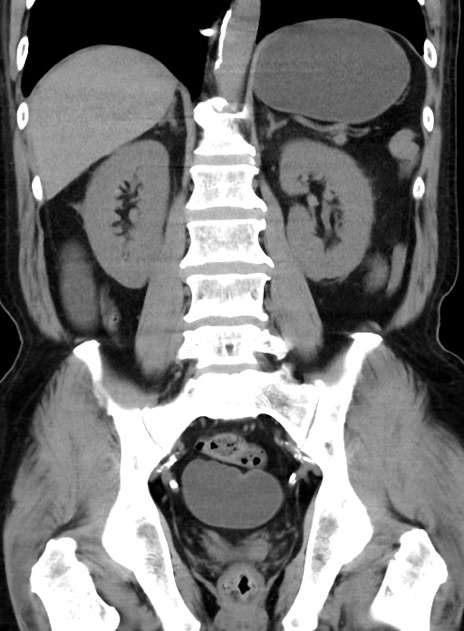

症例38(冠状断像)

【症例】70歳代 男性

【主訴】腹痛・嘔吐

【現病歴】昨晩より、嘔吐・腹痛あり。今朝になっても嘔吐あり。来院。

【既往歴】心臓バイパス手術、開腹胆摘、腸閉塞

【身体所見】BP 107/71mmHg、HR 116/min、腹部:平坦、軟、下腹部に軽度圧痛あり。反跳痛なし。

【データ】WBC 15100、CRP 0.32